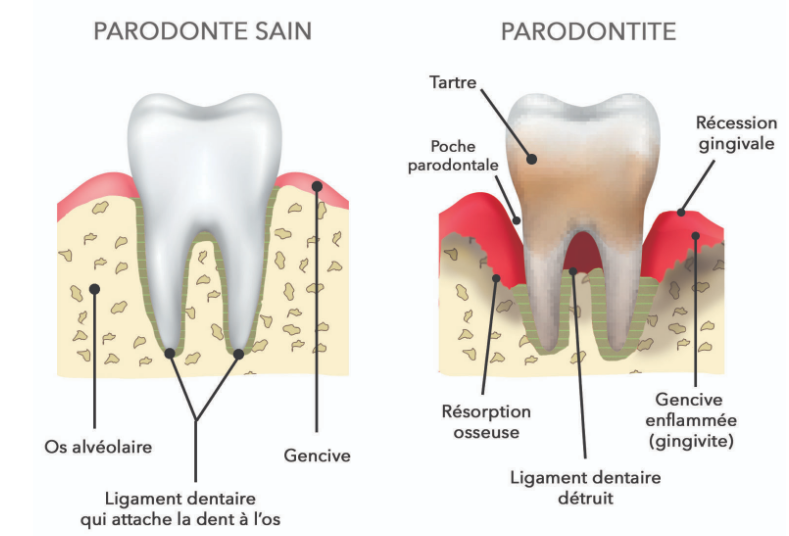

Les facteurs de risque modifiables qui contribuent à la parodontite comprennent :

⚠️ Il est souvent difficile de distinguer si une maladie est à l'origine de la parodontite ou si elle y contribue.

L'examen clinique dentaire et parodontal associé au sondage mesurant la profondeur des poches suffit généralement à établir le diagnostic. La radiographie dentaire met en évidence une perte d'os alvéolaire adjacente à ces poches.

La modification des facteurs de risque, tels qu'une mauvaise hygiène buccale ou le tabagisme, améliore considérablement les résultats. Chez les patients diabétiques, un contrôle strict de la glycémie est essentiel.